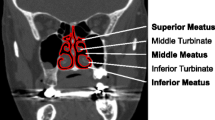

Patient-specific studies of physiological flows rely on anatomically realistic or idealized models. Objective comparison of datasets or the relation of specific to idealized geometries has largely been performed in an ad hoc manner. Here, two rational procedures (based respectively on Fourier descriptors and medial axis (MA) transforms) are presented; each provides a compact representation of a complex anatomical region, specifically the nasal airways. The techniques are extended to furnish average geometries. These retain a sensible anatomical form, facilitating the identification of a specific anatomy as a set of weighted perturbations about the average. Both representations enable a rapid translation of the surface description into a virtual model for computation of airflow, enabling future work to comprehensively investigate the relation between anatomic form and flow-associated function, for the airways or for other complex biological conduits. The methodology based on MA transforms is shown to allow flexible geometric modeling, as illustrated by a local alteration in airway patency. Computational simulations of steady inspiratory flow are used to explore the relation between the flow in individual vs. averaged anatomical geometries. Results show characteristic flow measures of the averaged geometries to be within the range obtained from the original three subjects, irrespective of averaging procedure. However the effective regularization of anatomic form resulting from the shape averaging was found to significantly reduce trans-nasal pressure loss and the mean shear stress in the cavity. It is suggested that this may have implications in attempts to relate model geometries and flow patterns that are broadly representative.

Doorly, D. J., D. J. Taylor, A. M. Gambaruto, R. C. Schroter, and N. Tolley. Nasal architecture: form and flow. Philos. Trans. R. Soc. A: Math. Phys. Eng. Sci. 366(1879):3225–3246, 2008.

Doorly, D. J., D. J. Taylor, and R. C. Schroter. Mechanics of airflow in the human nasal airways. Respir. Physiol. Neurobiol. 163(1–3):100–110, 2008.